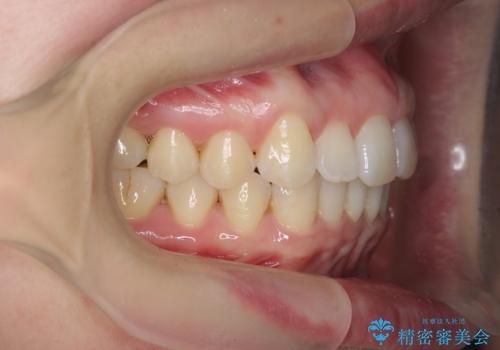

インビザライン で治す 出っ歯の治療

- 前歯の突出感、出っ歯の治療を希望され来院されました。

インビザラインを用いた治療計画を立て、しっかりと出っ歯を治すためにマイクロインプラントを併用します。

マイクロインプラントを併用することでしっかりとマウスピース全体を後方へ引き、前歯の突出感を改善することができました。